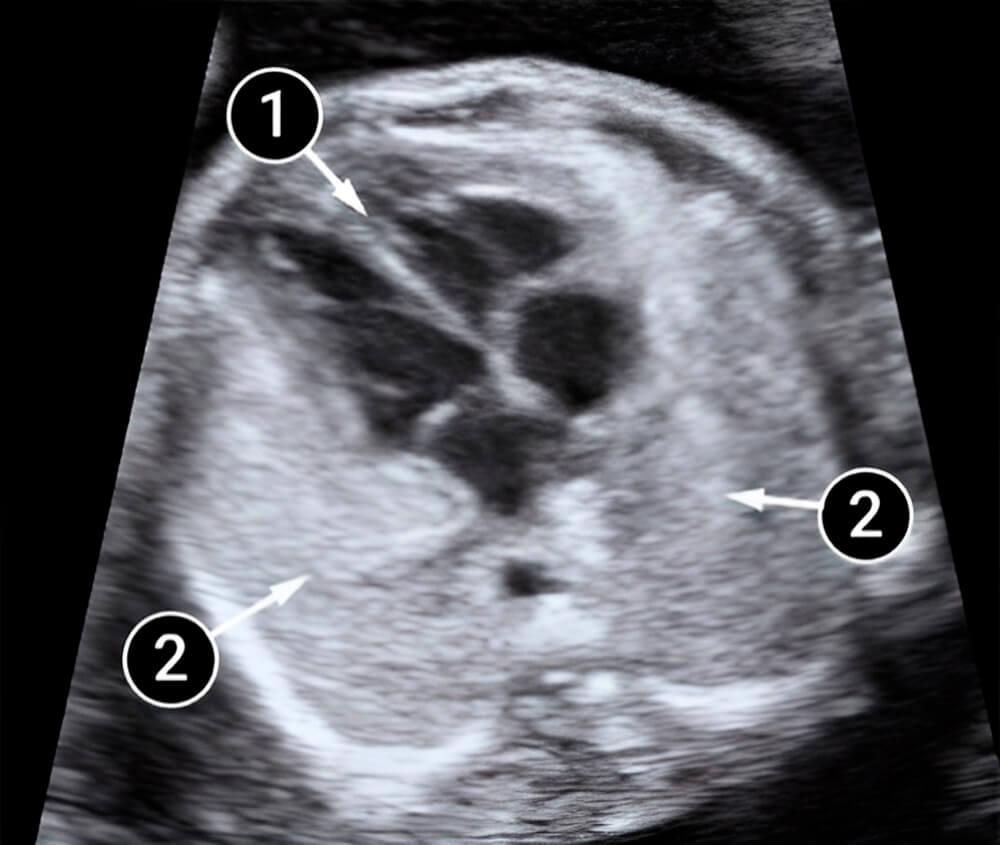

Lo que podemos ver en un ultrasonido

La imagen muestra una sección transversal del tórax. Los pulmones lucen blancos y el corazón es el área oscura en el medio de la imagen. El corazón ocupa casi un tercio del pecho. Se ven cuatro partes del corazón: dos aurículas y dos ventrículos, así como las separaciones entre ellos.